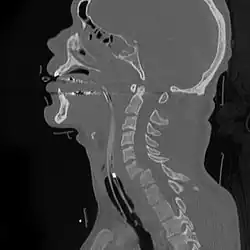

Teardrop fracture of C3 (sagittal CT)